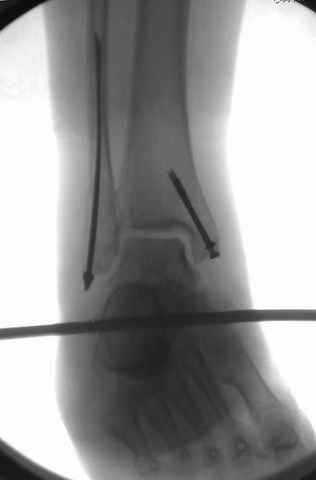

Отправитель: Djoldas Kuldjanov, M.D. 16 Сентябрь 2004, 22:00

Второй случай сделан из одного разреза

Дж

ЕЧ LISS plate, mininvasive approach - luxurous !

На прямой проекции послеоперационного Рг макроскопически все выглядит очень анатомично, при микроскопическом ( :-)) ) рассмотрении можно все-таки заметить вальгизацию тарана, суставная щель в латеральном отделе сустава несколько уже , чем в медиальном при отсутствии латерального смещения тарана. У меня был аналогичный случай (без LISS , без мини доступа) с вальгусным наклоном тарана при восстановленном ankle mortise при последовательном наблюдении с интервалами в 6-8 недель в послеоперационном периоде отмечалось прогрессирующее сужение суставной щели в латеральном отделе сустава, закончившееся посттравматическим ОА, к счастью боли умеренные, купируемые аналгетиками или своими эндорфинами:-))(активная пациентка, у которой нет времени на болезни....) Какова жизненная ситуация в приведенном вами случае? И последнее, что я хотел бы прояснить для себя - фиксация внутренней лодыжки: я обычно комбинирую фиксацию компрессирующим винтом со спицей - по идее ротационная стабильность должна быть лучше, чем один винт, каковы ваши наблюдения в этом плане?